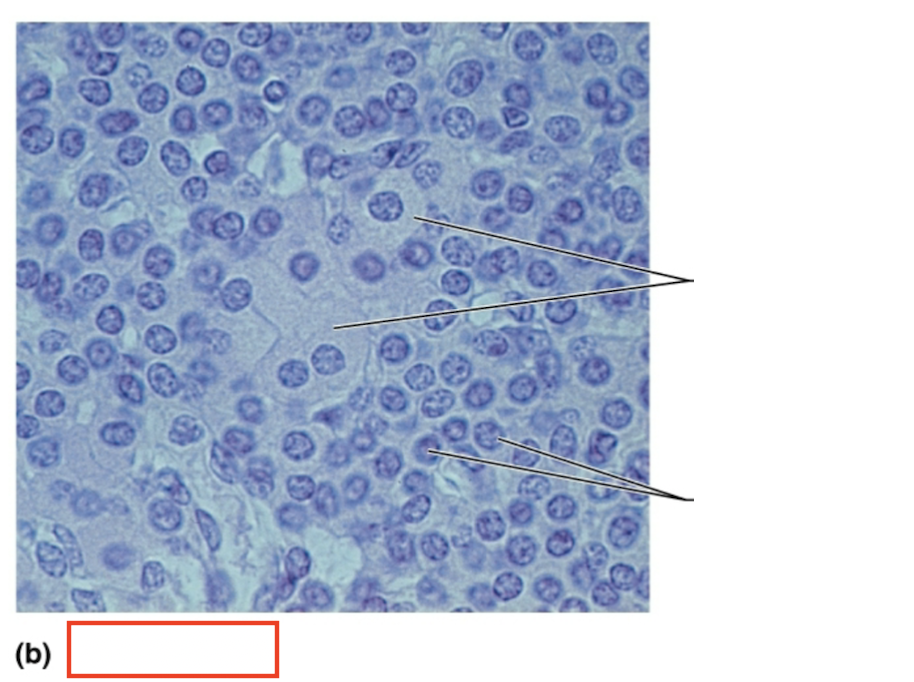

What structure is highlighted?

alpha cells (glucagon producing)

What structure is highlighted?

beta cells (insulin producing)

What structure is highlighted?

pancreatic acinar cells (exocrine)

What tissue is shown?

pancreatic islet

What hormones are released by the pancreas?

insulin, glucagon

What are the target organs and effects of insulin

most cells of the body, accelerates the transport of glucose into body cells; promotes glycogen, fat, and protein synthesis

What are the target organs and effects of glucagon?

primarily the liver and adipose; accelerates the breakdown of glycogen to glucose, stimulates the conversion of lactic acid into glucose, releases glucose into the blood from the liver

What stimulates glucagon production?

decreased blood glucose levels, sympathetic nervous system stimulation

What stimulates insulin production?

increased blood glucose levels, parasympathetic nervous system stimulation